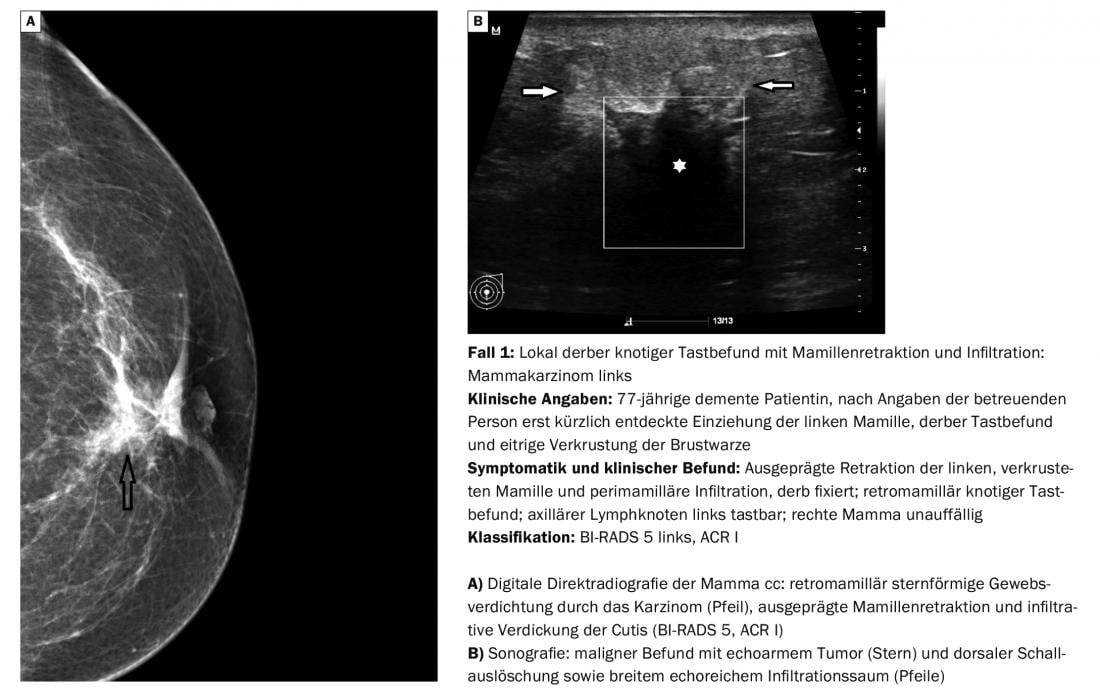

O diagnóstico diferencial dos nódulos mamários palpados corresponde em cerca de 90% a alterações benignas tais como fibroadenomas, cistos, mastopatias fibrocísticas e outras alterações mais raras. Contudo, o carcinoma é de esperar em cerca de 10% dos casos [1]. Os resultados da palpação nestes casos são geralmente nódulos grosseiros. As pequenas descobertas podem ainda ser móveis, os tumores maiores menos. Contudo, nem todas as malignidades são clinicamente evidentes (caso 2) ou, no caso de estrutura mamária densa e palpação suspeita, também podem ser claramente reconhecidas mamograficamente (caso 3).

Para além das imagens mamográficas e sonográficas, a tomossíntese digital está em vias de ser cada vez mais utilizada. Pode eliminar o mascaramento indesejável de resultados relevantes através de sobreposições estruturais e reduzir o número de resultados falsos positivos e falsos negativos da interpretação de imagens [2]. Em princípio, pode afirmar-se que a mamografia digital representa agora o padrão de diagnóstico em toda a linha e oferece vantagens consideráveis no pós-processamento (zoom, inversão, medições), para além da monitorização da visualização das imagens [3]. A RM mamária é utilizada com muito mais frequência para alterações malignas e é um instrumento fiável para diferenciar tecido cicatricial e tumores recorrentes – mesmo quando existe uma discrepância entre a clínica e a mamografia, por um lado, e a sonografia, por outro (caso 2). As indicações específicas para a utilização do método já foram descritas. No entanto, a RM ao seio é também um procedimento de diagnóstico tecnicamente muito exigente e propenso a erros; é importante evitar artefactos de movimento e erros de saturação de gordura ou tê-los em conta na avaliação [4].

Os diferentes tipos histológicos (panorâmica) de tumores limítrofes, semi-malignos e malignos nem sempre podem ser diferenciados imagem-morfológica-morfologicamente. É crucial que eles sejam reconhecidos e que o curso seja definido para procedimentos de diagnóstico ou terapêuticos posteriores, se necessário.